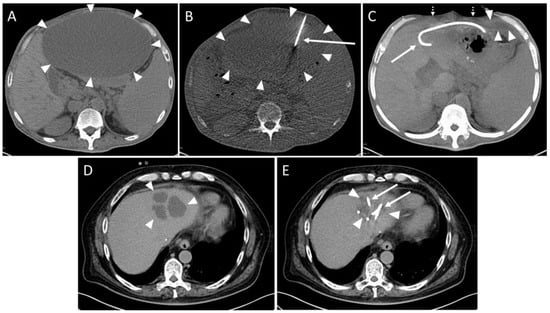

One intervention had to be aborted since the patient complained of pain exacerbation. No fluid could be aspirated in one session. In one case, the aspirate contained fresh blood. The drain was removed and subsequent control imaging examinations showed no active bleeding (SIR Grade A). In three cases, a small pneumothorax was observed in the control scan (SIR Grade A). The punction of a cystic fluid collection yielded a small hemorrhage without the need for therapy in one patient (SIR Grade A, Figure 3).

In one intervention, large amounts of blood were aspirated through the drainage. A gelatin slurry (Gelofam) was applied via the drainage which successfully stopped the bleeding (SIR Grade C). After one intervention, an immediate revision surgery was re-quired due to an accidentally injured artery during the CTD placement (SIR Grade D, Figure 4).

In summary, five (5.5%) minor and two (2.2%) major complications were observed (Table 3). The technical success rate yielded 93.4% (85/91).

The insertion of a CTD can be associated with a range of complications of varying degrees of severity. Its main spectrum includes pneumothorax and bleeding, but sepsis or even death can also occur [5,16,19,21].

Akinci et al. demonstrated in a larger case series of 291 patients with drainable intraperitoneal abscesses a peri-complication rate of 12% [11]. In our study, the technical success rate was slightly lower. We observed seven patients (7.7%) with two classified as major complications according to the SIR guidelines [20]. This is in agreement to Wallace et al. [8] suggesting a threshold of less than 10%. A total of 93.4% of the interventions in our study were technically successful. This value is within the range from 88.9% to 100% found by other authors [7,10,13] and is also within the range of 93.0% to 100%, which we have achieved in studies involving other patient cohorts following abdominal interventions [26,27,28,29]. The most serious complication observed in our patient cohort was severe hemorrhage in one case, requiring immediate surgical intervention. The probable cause was presumed to be patient movement occurring between the acquisition of the planning scan and fluoroscopy scans. We conclude that a reduction in the incidence of complications may involve a more rigorous patient selection process and a broader utilization of conscious sedation or general anesthesia, particularly in the early postoperative period.